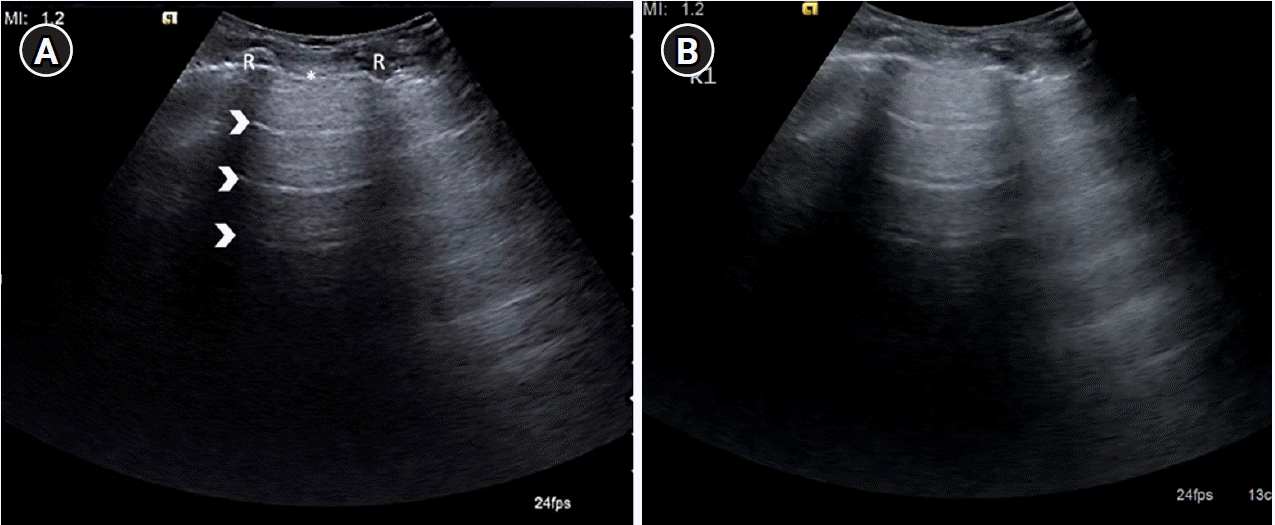

Figure 4.

(A) Longitudinal ultrasound scan of the second intercostal space in the mid-clavicular line on anterior chest wall depicting sonographic appearance of normal lung, identified by the landmarks forming the “bat sign”: two ribs (R) with posterior acoustic shadowing representing the wings of the bat, and the hyperechoic pleural line (asterisk), its body. A-lines (arrowheads) can be seen parallel to the pleural line. (B) Cine US clip depicting the same (Supplementary Material 1).